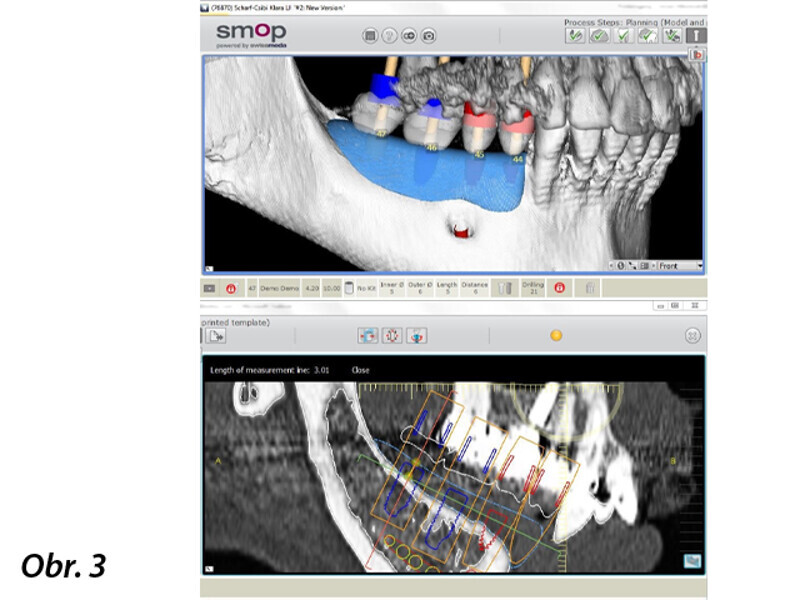

Horizontální augmentace hřebene a implantace: Dvoufázová procedura GBR